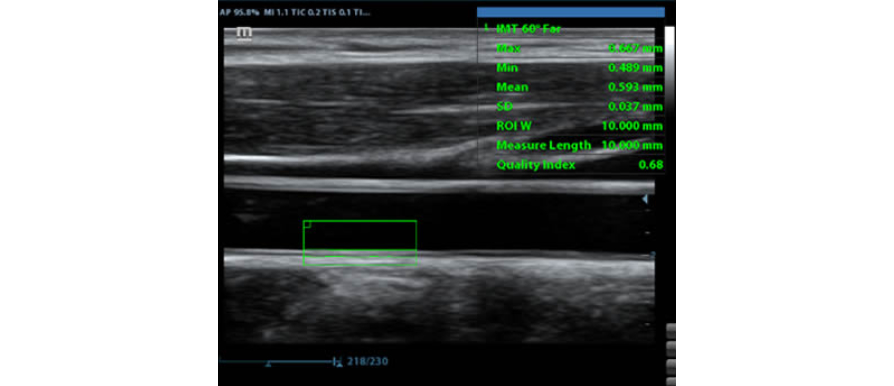

IMT (Intima-Media Thickness)

Automatyczny pomiar grubo?ci kompleksu Intima-Media na przedniej i tylnej ?cianie naczynia, umo?liwia precyzyjn? ocen? stanu t?tnicy szyjnej.